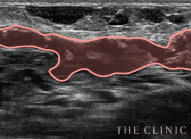

しこりの状態

アクアフィリング豊胸やアクアリフト豊胸では被膜が形成されにくいはずですが、そうでない症例も見られます。反対に、しこり化していないケースでは組織と注入成分を見分けます。

厚い被膜

ヒアルロン酸より組織へのなじみが良く、被膜が形成されにくいと言われるアクアフィリング豊胸やアクアリフト豊胸でも、実際には非常に厚い被膜が確認されています。

広がるしこり

アクアフィリング豊胸やアクアリフト豊胸は、しこりが散在するケースが見受けられます。注入方法によるものか性質上の問題なのか、原因は定かではありません。

形がいびつなバスト

アクアフィリング豊胸やアクアリフト豊胸後には、触感が硬くなるだけでなく、胸の形までもいびつになるという被害が報告されています。